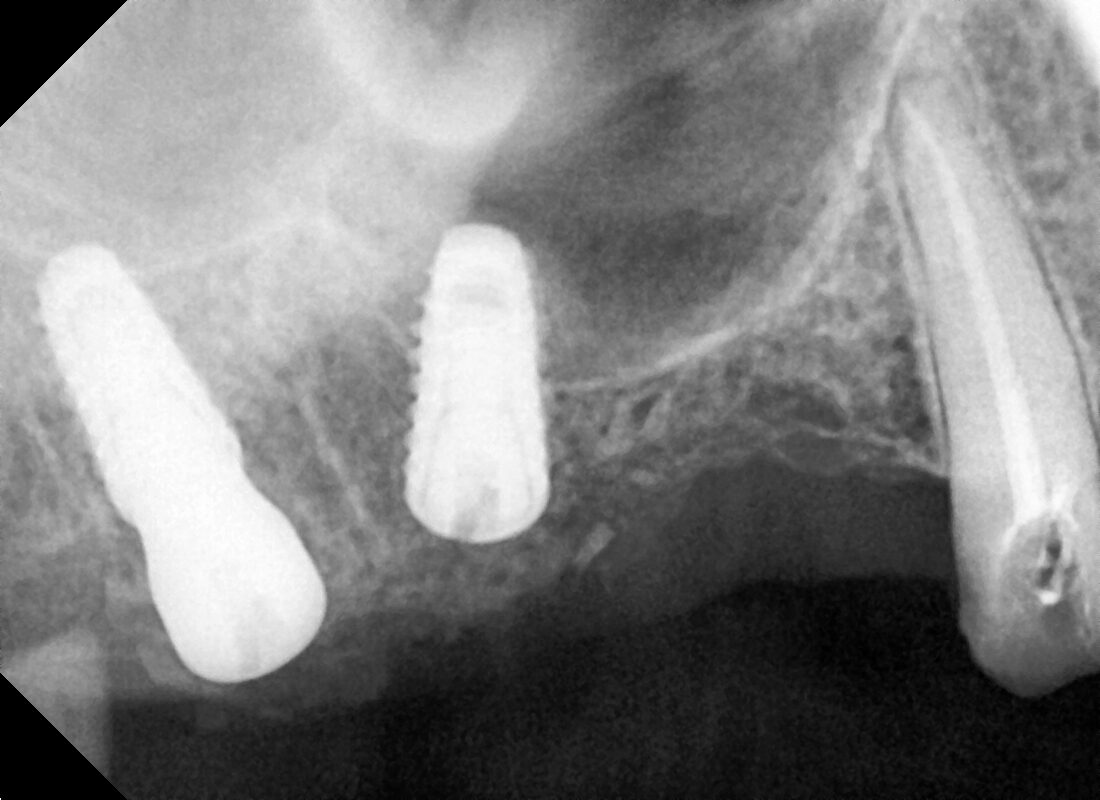

TWO IN MANDIBULAR ARCH